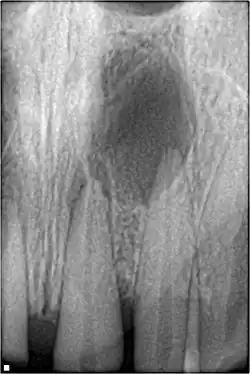

Radiographic signs of periapical inflammation is usually evident in a tooth with necrotic pulp

Root resorption

Root resorption following traumatic dental injuries, whether located along the root surface or within the root canal appears to be a sequel to wound healing events, where a significant amount of the PDL or pulp has been lost due to the effect of acute trauma.[43]